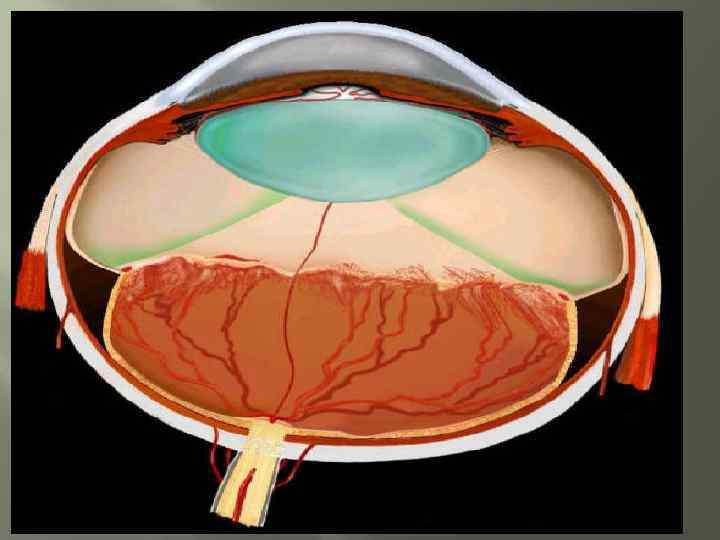

Патогенез Продолжающееся распространение этих сосудисто-пролиферативных элементов к сетчатке и, в некоторых случаях, в стекловидное тело приводит к появлению кровоизлияний Способствует фиброзу и разрастанию глиальной ткани с последующими витреоретинальными тракциями и окончательной отслойки сетчатки.

Патогенез Продолжающееся распространение этих сосудисто-пролиферативных элементов к сетчатке и, в некоторых случаях, в стекловидное тело приводит к появлению кровоизлияний Способствует фиброзу и разрастанию глиальной ткани с последующими витреоретинальными тракциями и окончательной отслойки сетчатки.

Классификация Частичная отслойка сетчатки; Полная отслойка сетчатки.

Классификация Частичная отслойка сетчатки; Полная отслойка сетчатки.

Лечение Хирургическое лечение - применяют при быстропрогрессирущих, далекозашедших стадиях(4 -5 стадия и «плюс» -болезнь) Склеропломбирование- установка с внешней стороны глаза «заплатки» которая придавливает стенки глаза к отслоившейся сетчатке. Эффективна при небольших отслойках. Благоприятным исходом можно считать улучшение зрения либо остановку ухудшения зрения Витректомия - удаление стекловидного тела. Применяется при больших отслойках сетчатки и массивных кровоизлияниях в стекловидное тело, а так же при неэффективности пломбирования склеры. Т. к. выполняется при серьезных изменениях сетчатой оболочки прогноз не всегда благоприятный.

Лечение Хирургическое лечение - применяют при быстропрогрессирущих, далекозашедших стадиях(4 -5 стадия и «плюс» -болезнь) Склеропломбирование- установка с внешней стороны глаза «заплатки» которая придавливает стенки глаза к отслоившейся сетчатке. Эффективна при небольших отслойках. Благоприятным исходом можно считать улучшение зрения либо остановку ухудшения зрения Витректомия - удаление стекловидного тела. Применяется при больших отслойках сетчатки и массивных кровоизлияниях в стекловидное тело, а так же при неэффективности пломбирования склеры. Т. к. выполняется при серьезных изменениях сетчатой оболочки прогноз не всегда благоприятный.